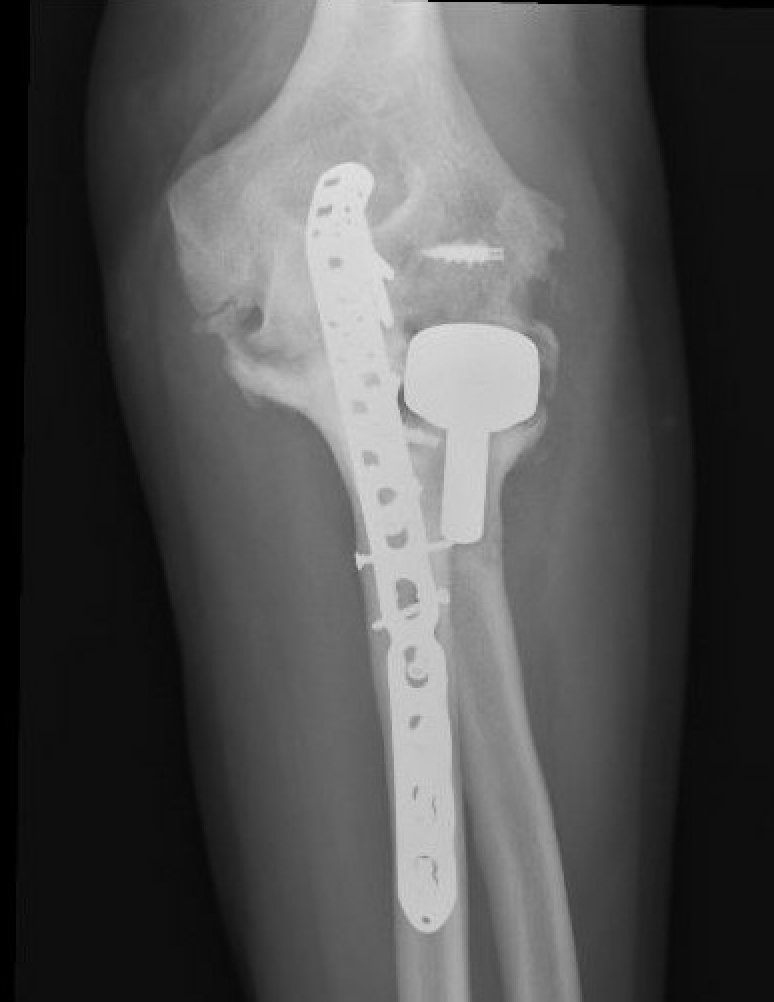

Olecranon plate + ORIF Type II coronoid process + radial head replacement

Olecranon plate with radial head replacement

Olecranon plate with radial head replacement + LCL repair

Olecranon plate + medial coronoid buttress plate + radial head replacement

Complex proximal ulna fracture with radial head replacement subluxation